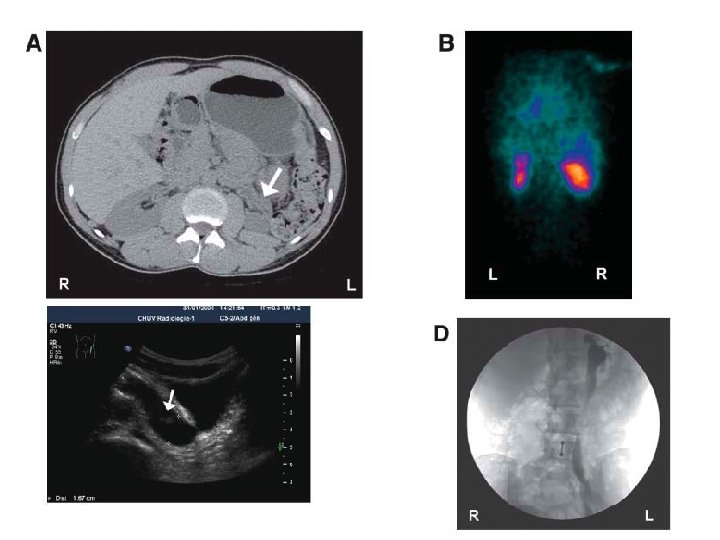

35 year-old : Doppler ultrasound showing parvus-tardus pattern with collapsed resistance index Normal right kidney

Left kidney Right kidney

75 year-old lady – OIH study

Typical diagnostic workup for RVH Doppler sonography, CT angiography or MRA ACE inhibitor renography Renal angiography and treatment